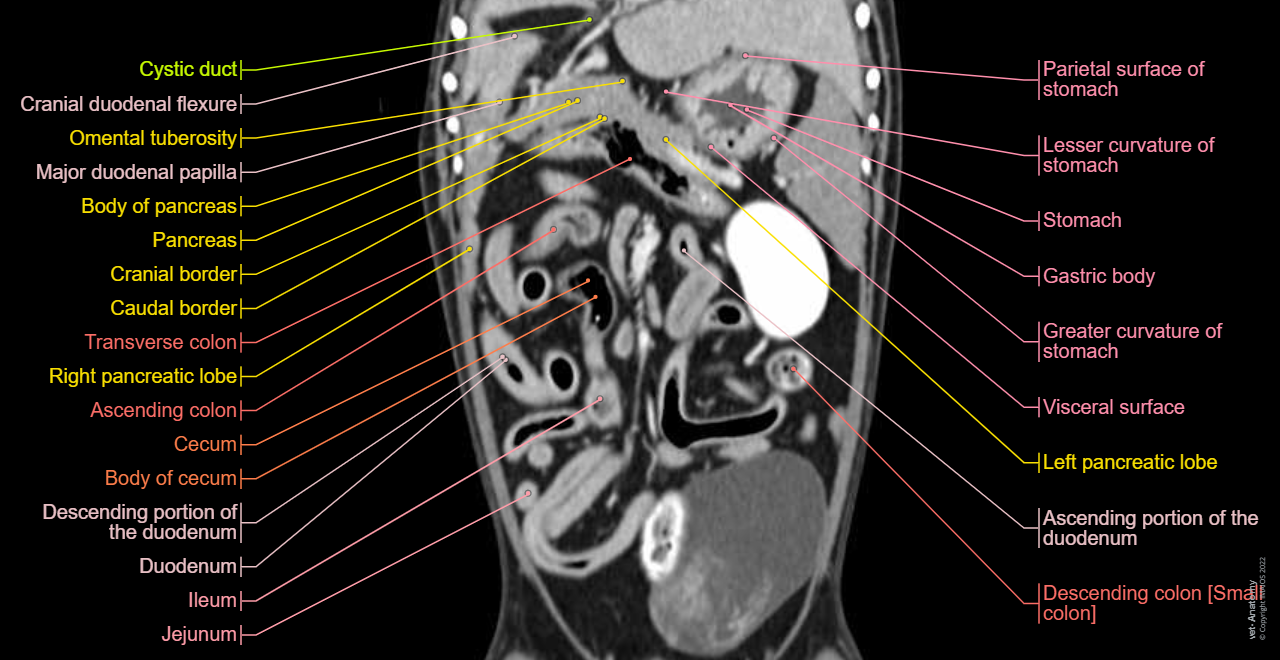

Cross-sectional labeled anatomy of the abdomen and male pelvis of the dog on CT imaging (liver, hepatic segmentation, pancreas, biliary tract, digestive tract, small and large intestine, kidney, bladder, genital organs, peritoneum)

Anatomy of the male canine abdomen and pelvis on CT imaging: Alimentar canal, Stomach, Colon

Dog - Digestive system - 3D - Anatomy: Stomach, Duodenum, Jejunum, Ileum, Small intestine, Large intestine, Colon, Rectum